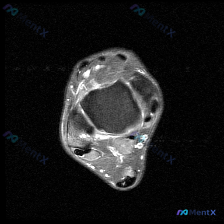

病例基本信息 这是一份膝关节MRI的读片病例,提供的是单张放射影像-膝盖MRI-T1序列-轴位图像,临床方向指向「怀疑存在软骨异常」,我们先整理影像观察结果: 影像学观察结果 1. 基本图像信息:这是轴位T1加权成像,骨髓脂肪呈高信号,软骨和血液呈低/中等信号,适合观察解剖结构完整性 2. 骨骼结构...

分享一张踝关节MRI轴位T2加权图像的读片思路,整理出来和大家一起讨论。 一、基本影像信息 本次提供的是单张踝关节MRI轴位T2加权(脂肪抑制/液体敏感序列)图像,先整理客观读片结果: 1. 骨骼结构:胫骨腓骨远端横断面可见,骨髓无异常高信号(无骨挫伤),骨皮质完整,无骨折线也无侵蚀性骨破坏 2....

今天整理了一例踝关节MRI读片病例,核心问题是问「软骨异常有什么发现」,看完图像发现挺有代表性,整理出来和大家分享思路。 一、影像基本信息 这是踝关节MRI T2序列轴位图像,层面位于踝关节平面,可以看到胫骨远端(内踝)、腓骨远端(外踝)和距骨横截面: 1. 骨结构:胫距关节面形态完整,没有明显骨折...